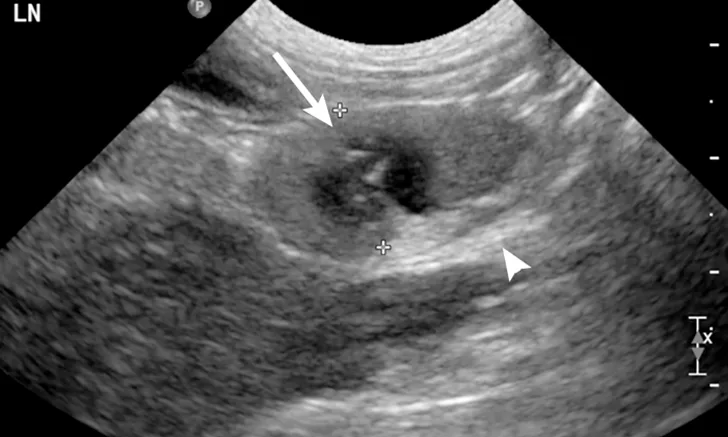

Ultrasound image of a jejunal lymph node. A moderately enlarged lymph node with a rounded heterogeneous appearance and ill-defined hypoechoic patches can be seen (arrow). The mesenteric fat around the lymph node was diffusely hyperechoic (arrowhead).

Abdominal ultrasonography revealed the presence of multiple enlarged, heterogeneous, and rounded cranial mesenteric lymph nodes (Figures 1, above, and 2). These findings were suggestive of round cell neoplasia, lymphadenitis (infectious or noninfectious), or reactive lymphadenopathy. There was a small amount of free abdominal fluid, which was sampled and submitted for analysis; this was compatible with a nonseptic suppurative exudate. Culture results of the fluid were negative. Fine-needle aspirates and cytology of the abdominal lymph nodes were consistent with neutrophilic lymphadenitis (Figure 3). No infectious agents were seen. The rest of the abdominal ultrasound was unremarkable.